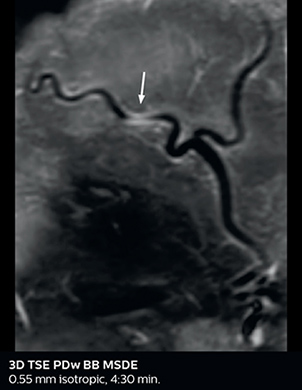

Dr. Savatovsky appreciates the improvements and flexibility that Elition with Compressed SENSE and MultiBand SENSE provides, particularly for stroke patients. “For stroke, it allows us to cut about 5 minutes off of our stroke protocol, or to keep the same acquisition time and get more insights.” The ability to perform more sequences can help in making a swift and confident diagnosis. “For example, our stroke cases usually include the regular sequences that every center does (b1000 diffusion, FLAIR, time-of-flight angiography), but we also image supra aortic vessels, and we can replace a gradient echo sequence with a fast 50-second susceptibility-weighted sequence, and all of this doesn’t add much time. because all the regular sequences are accelerated on Elition.” “The time savings with Compressed SENSE and MultiBand SENSE make it easier to add sequences to give us additional insights. Depending on the context and the first results, we might add a DSC perfusion to assess the ischemic penumbra, an ASL perfusion to help find an alternative cause in case of normal diffusion, or add a high-resolution T1 sequence for a stroke patient, to quickly assess wall imaging in emergency cases. The additional sequences can help improve patient management, because we can already consider some alternative diagnoses if the morphological MRI is normal.”

Using MultiBand SENSE allowed the staff to improve their diffusion quality. “Our diffusion sequence was already fast before, about 40 seconds. Now with Elition, it still lasts 40 seconds, but we improved the spatial resolution by 0.2 mm and use high b-values to be more sensitive to visualize changes related to acute stroke,” says Dr. Savatovsky. “We now also developed a high resolution DTI sequence (1.3 x 1.3 x 2 mm) that can be reformatted and takes 2 to 5 minutes depending on the coverage. We use it every time we have a doubt, or when we expect the diffusion to be abnormal but don’t see that on the fast sequence. We occasionally spot small ischemic infarctions that would not have been visible with the regular diffusion sequence.”

This is an example of acute ischemic stroke with distal occlusion of the right posterior cerebral artery. Note the improved visibility of the ischemic territory on the diffusion weighted image with high b-value. The 3D FLAIR shows a distal PCA occlusion. The fast SWIp depicts the thrombus on the isolated second echo image. The total scan time (including SmartBrain, preparations and a fast 3D T1w TSE Gd) is 8:00 minutes.

In this patient with acute right motor deficit and aphasia, the b2000 diffusion weighted image is normal. The SWIp image demonstrates more prominent veins in the right hemisphere, which could reflect increased deoxyhemoglobin contents. Fast ASL shows low CBF regions in the left frontal lobe. A follow-up ASL after one hour demonstrates high CBF values in the same area. The final diagnosis was migraine with aura.